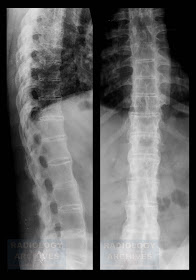

Απλή Ακτινογραφία (Rx): σε

πρώιμα στάδια μπορεί να είναι φυσιολογική (10%) ενώ η δύσπνοια προηγείται των

ακτινολογικών αλλοιώσεων: αμφοτερόπλευρες διάμεσες ή τύπου θαμβής υάλου

διηθήσεις, με παραπυλαία εντόπιση στα μέσα και κατώτερα πνευμονικά πεδία. Οι

διηθήσεις μπορεί να εξελιχτούν ραγδαία

και να προσβάλουν ολόκληρο τον πνεύμονα.[6] Σε όψιμο στάδιο, η νόσος

μιμείται πνευμονικό οίδημα.[2] Πλευριτική συλλογή (ασυνήθης).